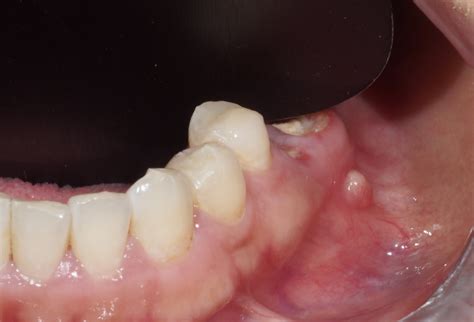

Tratamientos para una fístula dental

Una vez realizado el diagnóstico, el tratamiento dependerá de la causa subyacente y la gravedad de la infección. El tratamiento de una fístula dental se centra en eliminar la infección y restaurar la salud del diente afectado. En algunos casos, puede ser necesario drenar el absceso para aliviar el dolor y la presión. En la mayoría de las fístulas, es imprescindible la toma de medicación antibiótica.

- Drenaje del absceso: En los casos menos graves de fístula dental, es posible que el enfoque inicial sea un tratamiento conservador. El dentista puede realizar un drenaje incidiendo el absceso para permitir que el pus y los desechos se eliminen del área afectada.